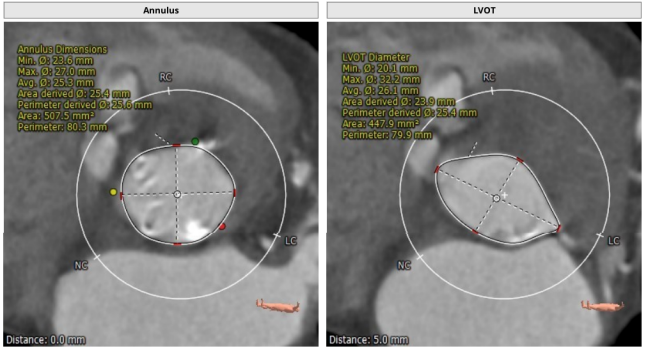

患者为功能型二叶瓣,重度钙化,左右融合,瓣环平面可见钙化延伸至左室流出道,冠脉高度高,法式窦结构大,心脏角度约51°,心肌增厚。

瓣环平均直径:25.6 mm,左室流出道平均直径:25.4 mm,升主动脉未见明显扩张,心脏角度:51°

钙化积分:832 mm³,重度钙化

术前CT评估提示

TYPE1型二叶瓣,重度钙化,左右可见钙化融合脊,法式窦结构可,双冠高度可,升主动脉增宽,最宽处约46 mm,心脏角度不大,左室大,心尖部可见囊状造影剂填充,考虑多系小室壁瘤,术中需谨慎操作,主动脉弓部走行较平缓。

瓣环平均直径:21.9 mm,左室流出道平均直径:21.6 mm,钙化积分:865.9 mm³

左冠开口高度:11.8 mm,右冠开口高度:13.4 mm